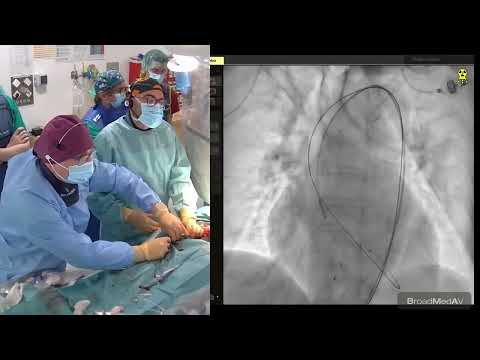

Transfemoral TAVR Evolut-R (29 mm) via Percutaneous Femoral Access - Structural Live March 2017